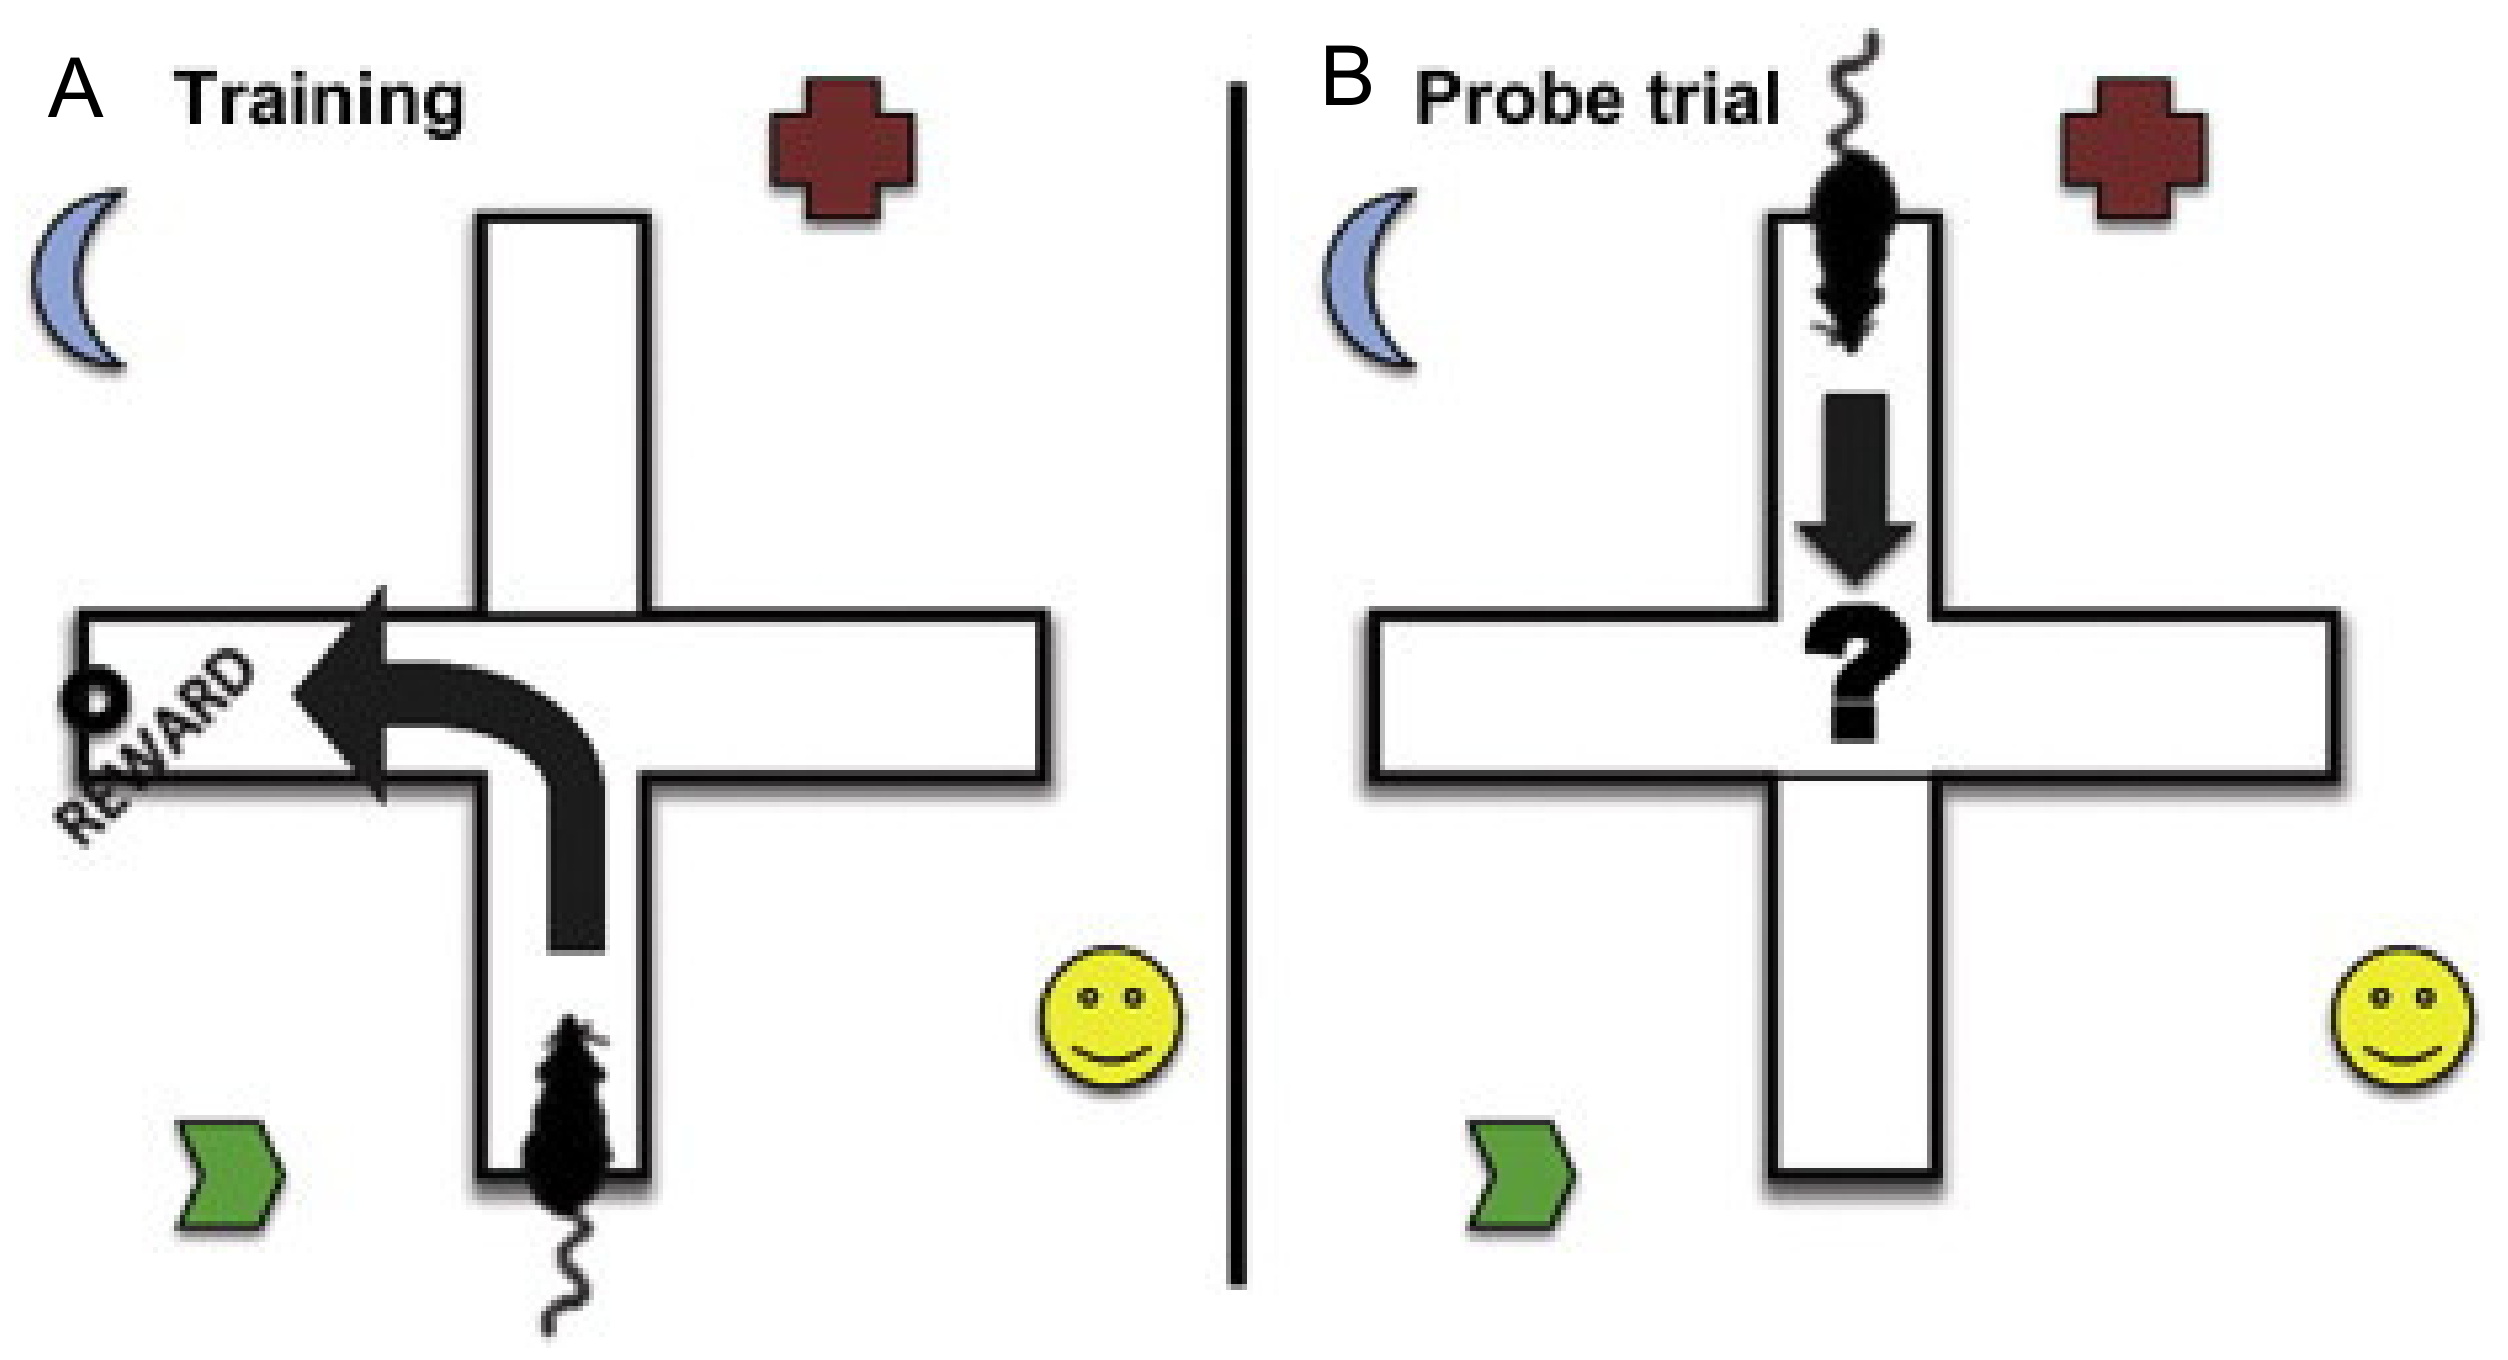

9.3. T and Y Maze

| Place Versus Response Learning | When the direction of the entrance arm is switched, the animal will either use spatial learning and turn toward goal or nonspatial learning and turn the direction turned during training. | TBI should more often use nonspatial learning and turn in the direction it did during training | This shows the difference between place learning (spatial learning) and response learning (nonspatial learning). | |